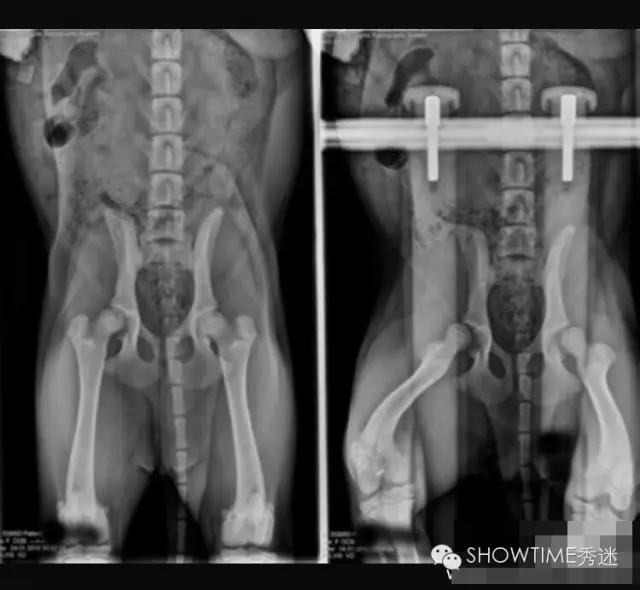

对于髋关节发育不良的判定,犬类骨科疾病种类很多,并非所有走路摇摆外八或者无力都是CHD。OFA策划是根据X光片来进行判断的,在犬只年满24月龄以后才会给出评判结果,24个月之前只做评估不做判定。因为犬在两岁前还在发育,股骨头和髋臼常会出现发育速度不一而产生髋关节发育不全的现象,这其中还要受到肌肉的影响。并且也有幼犬时期髋关节发育正常,而后随着成长过程发生严重变化,进而产生CHD症状,因此判定:只有在24月龄之后才可以做出。这是在美国和全世界至今应用最为广泛的方法,也是美国繁殖者在繁殖中的主要依托。

在髋关节发育不良的诊断中有一个最为重要的因素,就是X光片的拍摄要求。在国内很多医院因此而产生的误诊不胜枚举。